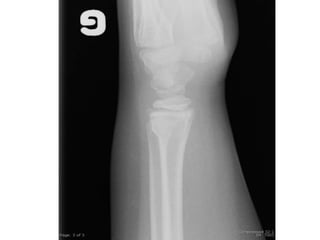

Diagnostic

A. Torus

B. Fx métaphysaire

C. Entorse

D. Salter 1

E. Salter 2

Salter 2

Réduction si rotation

Torus

• Buckle ou motte de beurre

• Fracture la plus fréquente en pédiatrie